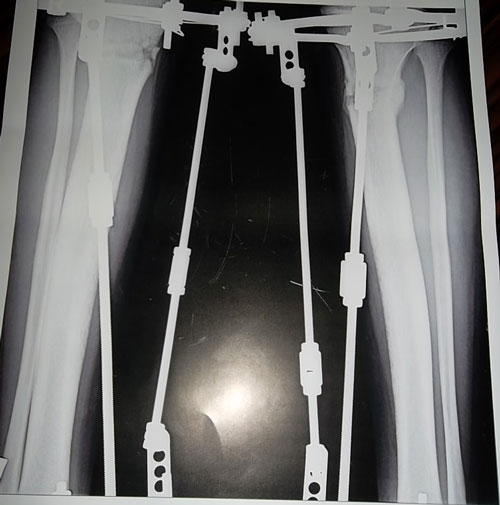

- Диагноз: О- образная деформация нижних конечностей

- Дата операции.: 30.01.2013

- Дата снятия аппаратов.: 04.05.2013

- Срок лечения.: 92 дня

На фиксации.Первый раз (на 23-ий день после операции) пошла без дополнительных средств опоры.

Первые самостоятельные шажки без дополнительных средств опоры на 23-ий день после операции.

Всем привет!Я с Алматы,мне 22.Приехала в Павлодар 24го сентября.25го утром сдала анализы,27го оперировали.После операций я не почувствовала боли и на следующий день я самостоятельно стала ходить с ходунком.Когда начила ходить были боли но терпимо.После операций на седьмой день вернее 4го ноября наш врач Н.Н начел крутить.Уже в тот день я увидела результат круток.Я в день ходила по 3,4часа.В общей сложности мне крутили ноги 15дней.А на последний день я увидела коласальный результат.На 23 день после операций начала ходить без ходунка.Спасибо нашему доктору.Руки у него золотые.Наконец-то мои мечты сбылись.И спасибо девченкам которые меня поддерживали.